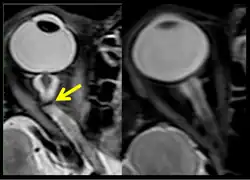

The third case of visual changes while on board the ISS had no changes in visual acuity and no complaints of headaches, transient visual obscurations, diplopia or pulsatile tinnitus during the mission. Upon return to Earth, no eye issues were reported by the astronaut at landing. Fundus examination revealed bilateral, asymmetrical disc edema. There was no evidence of choroidal folds or cotton-wool spots, but a small hemorrhage was observed below the optic dics in the right eye. This astronaut had the most pronounced optic-disc edema of all astronauts reported to date, but had no choroidal folds, globe flattening or hyperopic shift. At 10 days post landing, an MRI of the brain and eyes was normal, but there appeared to be a mild increase in CSF signal around the right optic nerve.[5]

The sixth case of visual changes of an ISS astronaut was reported after return to Earth from a 6-month mission. When he noticed that his far vision was clearer through his reading glasses. A fundus examination performed 3 weeks postflight documented a grade 1 nasal optic-disc edema in the right eye only. There was no evidence of disc edema in the left eye or choroidal folds in either eye (Figure 13). MRI of the brain and eyes days postflight revealed bilateral flattening of the posterior globe, right greater than left, and a mildly distended right optic nerve sheath. There was also evidence of optic-disc edema in the right eye. A fundus examination postflight revealed a "new onset" cotton-wool spot in the left eye. This was not observed in the fundus photographs taken 3 weeks postflight.[5]

The seventh case of visual changes associated with spaceflight is significant in that it was eventually treated postflight. Approximately 2 months into the ISS mission, the astronaut reported a progressive decrease in his near and far acuity in both eyes. The ISS cabin pressure, CO2 and O2 levels were reported to be within normal operating limits and the astronaut was not exposed to any toxic substances. He never experienced losses in subjective best-corrected acuity, color vision or stereopsis. A fundus examination revealed a grade 1 bilateral optic-disc edema and choroidal folds (Figure 15).[5]